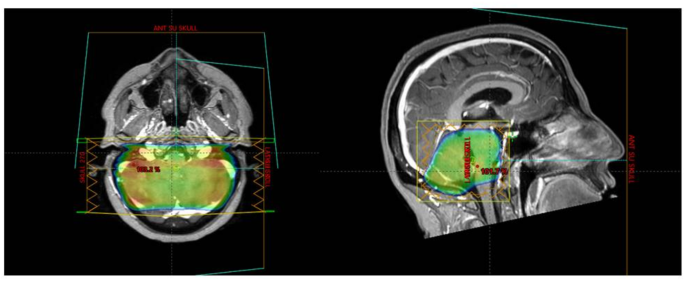

Clinical, dosimetric, and outcome data were collected and analyzed. Symptom data were extracted from patients’ files before treatment and three months after cerebellar radiation. Both volumetric arc therapy (VMAT) and 3D radiation planning were included, as well as all dose regimens. Dose constraints for re-cerebellar RT were set at an EQD2 of 72 Gy cumulative (combining the first and second radiation courses), with a point maximum for the brainstem and as low as reasonably achievable (ALARA) constraints for the cochlea, as previously cited11,12.

Breast cancer was the most common histology, affecting 40 patients. Other histologies included small cell lung cancer (8), ovarian adenocarcinoma (4), non-small cell lung adenocarcinoma (3), and melanoma (1). The median interval between WBRT and cerebellar RT was 15 months (range: 8–25). WBRT techniques included 3D planning in 85% of cases and VMAT with hippocampal avoidance in 15%. Most patients (92%) received 30 Gy in 10 fractions during WBRT, while the remainder received 20 Gy in 5 fractions (Figs. 1, 2 and 3).

Cerebellar RT was delivered using 3D and VMAT in 57.2% and 42.8% of the cohort, respectively. Systemic therapy was administered to 75% of patients during or before/after the RT course. Radiosurgery was performed for supra-tentorial lesions in 46% of patients after cerebellar RT, with a median of 5 lesions (range: 1–11) treated per patient. The median radiosurgery dose was 20 Gy (range: 16–24), delivered in single fractions.

The dose regimens for cerebellar RT were heterogeneous: 20 Gy in 10 fractions (21.4%), 25 Gy in 10 fractions (21.4%), 25 Gy in 5 fractions (17.8%), 24 Gy in 6 fractions (17.8%), 30 Gy in 12 fractions (10.7%), and 30 Gy in 10 fractions (10.7%). Table 1 shows a median follow-up duration of 14 months (range: 6–23). Symptomatic therapy with dexamethasone, at dosages ranging from 2 mg to 16 mg daily, was provided to 67.8% (38) of the cohort before the second RT course.